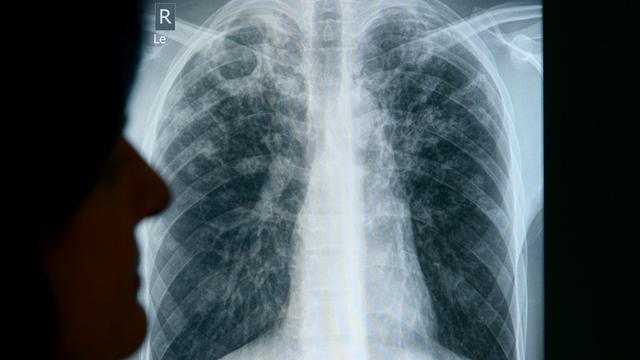

Im Zusammenhang mit einem Tuberkulose-Fall am Beruflichen Schulzentrum "Konrad Zuse" (BSZ) in Kamenz hat das Gesundheitsamt eine weitere Ansteckung festgestellt. Die betroffene Person befindet sich aktuell in stationärer medizinischer Behandlung, wie das Amt mitteilte. Weitere Untersuchungen bei 140 Kontaktpersonen werden durchgeführt. Der Schulbetrieb am BSZ kann demnach aber weiterhin uneingeschränkt fortgeführt werden. Für die Allgemeinbevölkerung besteht nach aktueller Einschätzung keine erhöhte Gefährdung. Tuberkulose ist eine Infektionskrankheit, die durch Bakterien verursacht wird und überwiegend die Lunge betrifft. Sie wird übertragen, wenn infizierte Menschen beim Husten und Niesen Erreger ausscheiden. Ohne Behandlung stirbt nach Angaben der Weltgesundheitsorganisation etwa die Hälfte der Infizierten. Mit einer vier- bis sechsmonatigen Behandlung können rund 85 Prozent der Menschen geheilt werden. © dpa-infocom, dpa:260126-930-597940/1